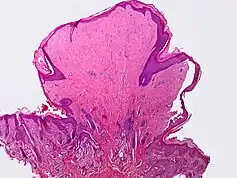

- Condyloma acuminatum